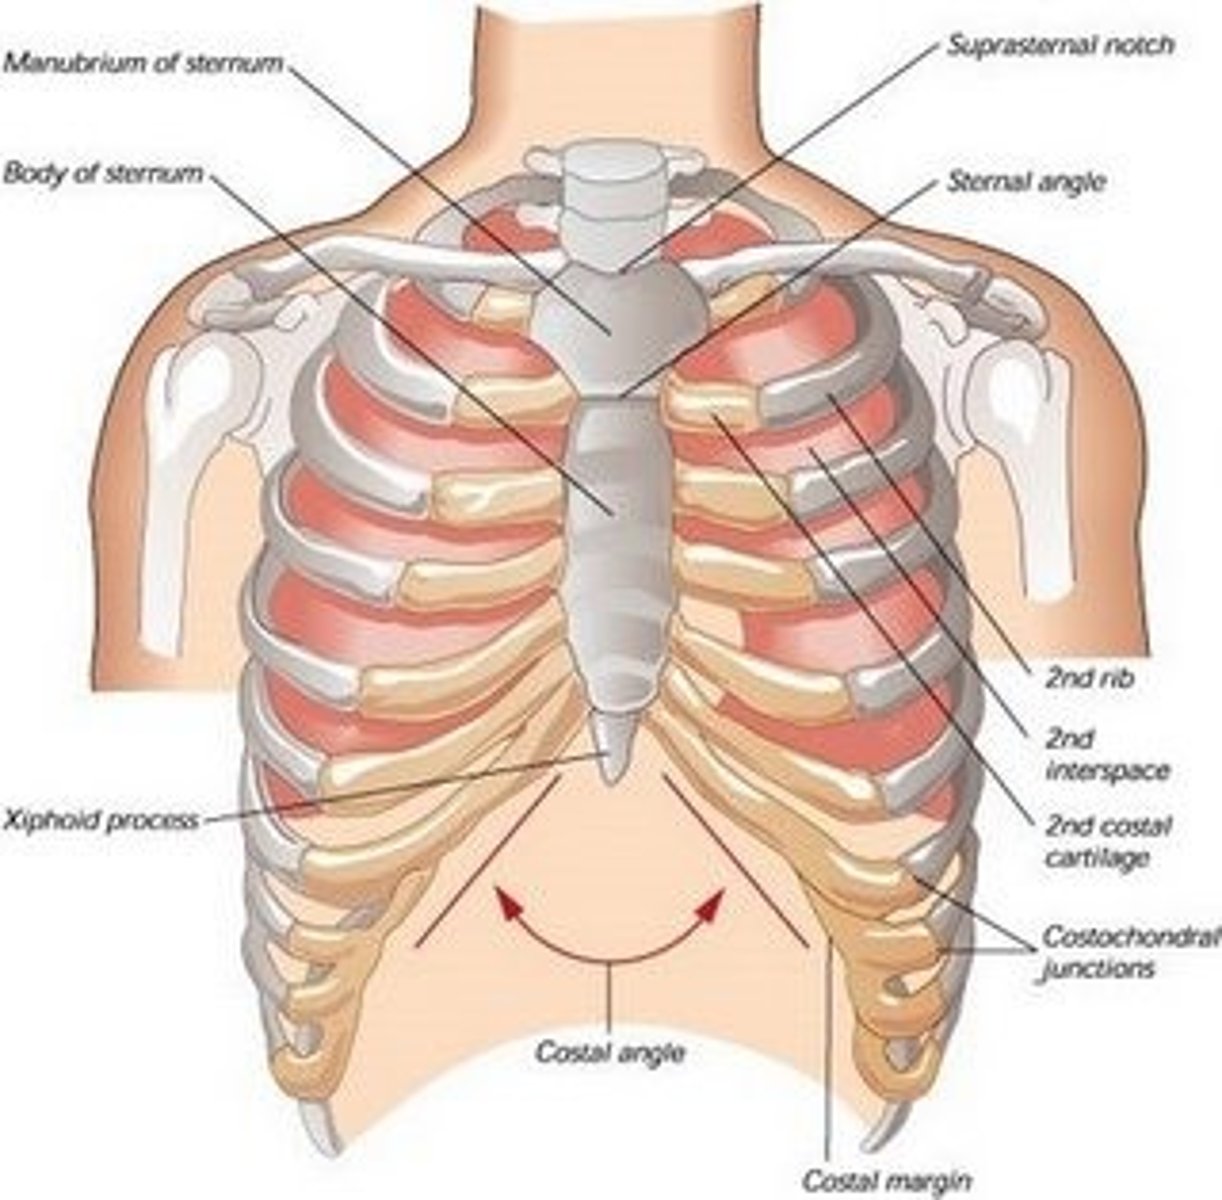

What makes up the thoracic cage?

sternum, ribs, and thoracic vertebrae

manubrium of sternum

suprasternal (jugular) notch

superior surface of manubrium; u shaped notch

clavicular notch of sternum

Site where manubrium articulates with the clavicles

costal notches of sternum

indentations on sternum where costal cartilages from the ribs articulate

sternal angle

Ridge between manubrium and body at second rib

Xiphoid process of sternum

(T10)

Midline marker for superior level of liver, central tendon of diaphram

inferior border border of heart

cartilaginous in young people. Bone after 40.

How is the costal cartilage numbered?

by the rib it articulates with

How are intercostal spaces numbered?

According to the rib superior to the space